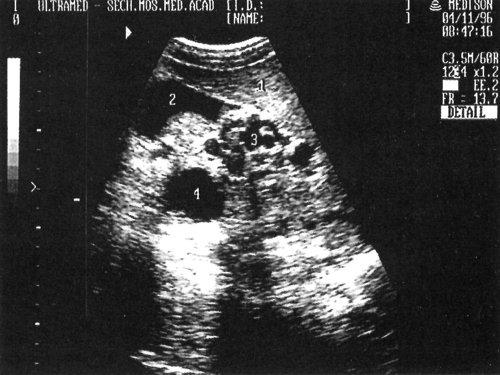

Рис. 8. Эхографическая картина порто-кавальных анастомозов в воротах печени: 1 - печень, 2 - желчный пузырь, 3 - порто-кавальные анастомозы, 4 - киста печени.